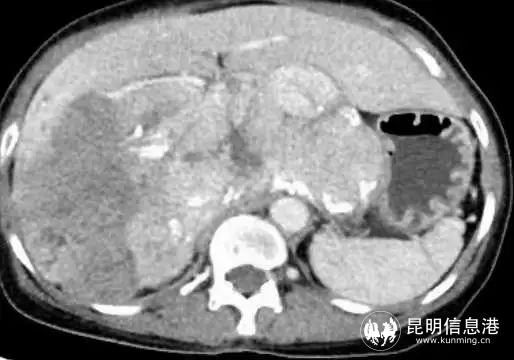

57歲的吳女士,從今年年初開始,感覺體力不斷下降,白天易疲勞,提不起精神,胃口也不好,體型日漸消瘦,不久出現(xiàn)右上腹隱約疼痛癥狀。家人送醫(yī)后CT檢查結(jié)果顯示:中、上腹巨大不均質(zhì)腫物,填塞肝門,貼壓膽囊、胰腺、右腎、門靜脈、下腔靜脈,考慮惡性。

圖為術前影像

患者入院后,省三院肝膽胰外科專家團隊經(jīng)過仔細檢查后發(fā)現(xiàn)該患者中上腹巨大不均質(zhì)腫物已經(jīng)填塞肝門,與肝實質(zhì)分界不清,貼壓膽囊、胰腺、右腎、門靜脈、下腔靜脈,手術操作的空間非常小。其次,患者身體基礎條件十分不好,長期高血壓,心肺功能極差,肝功能下降,手術難度極大。